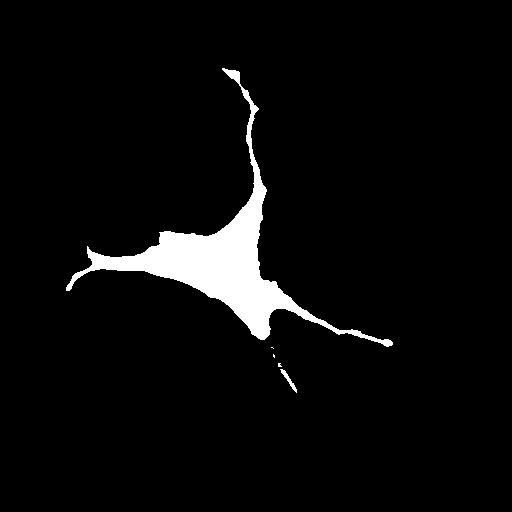

We evaluate the performance of each approach with five classical metrics: intersection over union (IoU), Dice score, precision, recall, and Hausdorff Distance (HD). We provide results on datasets , , and in Tables 1, 2, and 3, respectively. In Figure 2, we also illustrate representative segmentation results on dataset for each methods.

Raw

GT

U-net

CE-net

Attention U-net

AURA-net

The original U-net model produces poor segmentation results on datasets and while performing better on dataset . CE-net performs better than U-net and results in a strong recall in all three datasets. Attention U-net outperforms both CE-net and U-net on most metrics. The Attention gates incorporated in AURA-net allow outperforming CE-net, while its pre-trained layers help improve over Attention U-net. On top of that, the AC loss provides the network with additional information on object regions. As a result, AURA-net generally outperforms competing approaches. It occasionally scores closely to Attention U-net and CE-net, and even concedes a lead on recall in datasets and and on precision in dataset . It however performs best overall, with a consistent clear advantage on the IoU, Dice, and HD metrics.